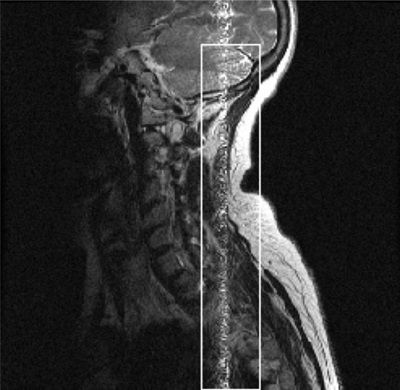

The following FSE sagittal cervical spine image displays an annefact. The image was acquired with a 24 cm FOV and the phase and frequency swapped. The artifact could have been prevented by not swapping phase and frequency and using a 2-coil selection, such as CS12 so the surface coil coverage would closer match the scan FOV.

Figure 1. FSE Cervical Spine with annefact